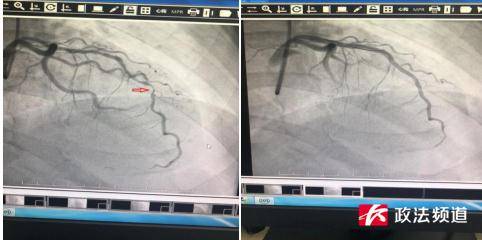

冠状动脉造影显示 , 奚先生的冠状动脉前降支已经堵塞了近95% , 几乎就剩下一条线了 。 随后 , 王勇为奚先生置入了3枚支架 , 闭塞的血管被成功开通 , 牙痛的症状也随即消失了 。

▲(图为奚先生支架手术术前、术后对比 , 箭头处为前降支血管约有95%的狭窄)